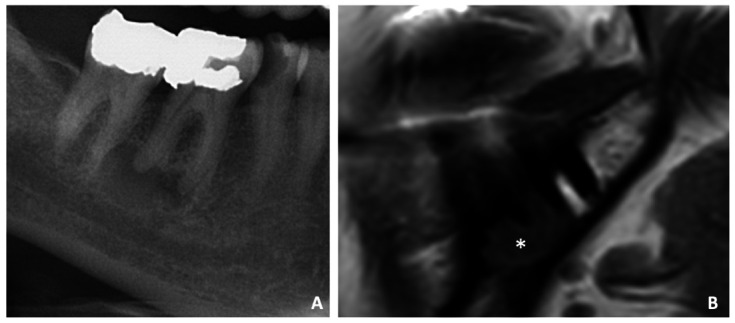

Abstract Image